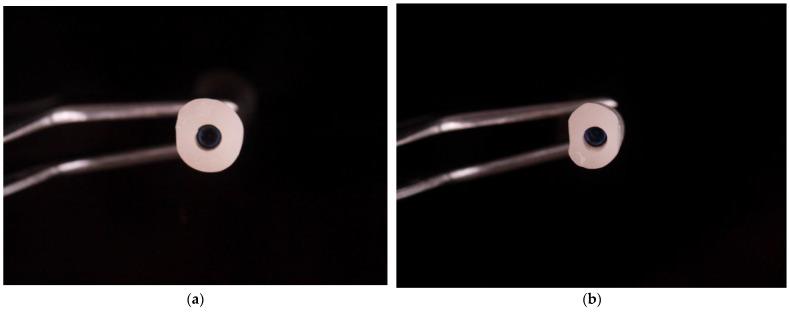

The obtained results allowed to design and create the shape of the anatomic healing abutment.

所得结果有助于设计并制作解剖型愈合基台的形状。